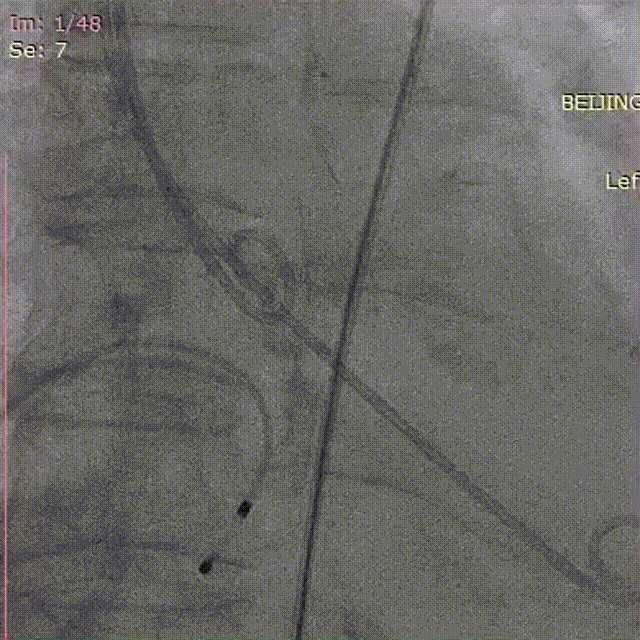

从三叶瓣重度钙化到二叶瓣畸形的根部解剖,从单纯主动脉瓣反流到入路极端迂曲挑战的案例。TaurusOne凭借其优异的柔顺性,支撑力强及内外层双侧裙边的特点,都能从容应对复杂的临床患者解剖结构。从患者的临床选择到术后的长久获益,从手术入路的种类到术中操作的注意事项,从围术期卒中的循证医学到术后的抗凝抗栓用药规范,在线专家共同交流彼此中心的围术期TAVR经验和分享现阶段经导管主动脉瓣置换的诊疗策略。针对当前TAVR领域多个热点学术问题进行了热烈的讨论,现场可谓精彩纷呈、高潮迭起。专家们纷纷借此契机相互交流探讨,分享各自的单中心经验,力求进一步提升TAVR手术的安全性和有效性,为主动脉瓣相关疾病的患者带来长远综合获益。